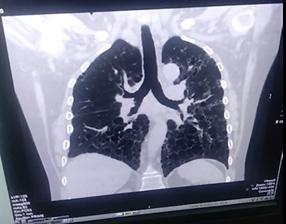

Paciente COVID-19 con trombosis e infarto agudo de miocardio

Reporte de Caso Clínico

COVID-19 patient with thrombosis and acute myocardial infarction

Rommer Alex Ortega Martínez

Gabriela Vaca Mendoza